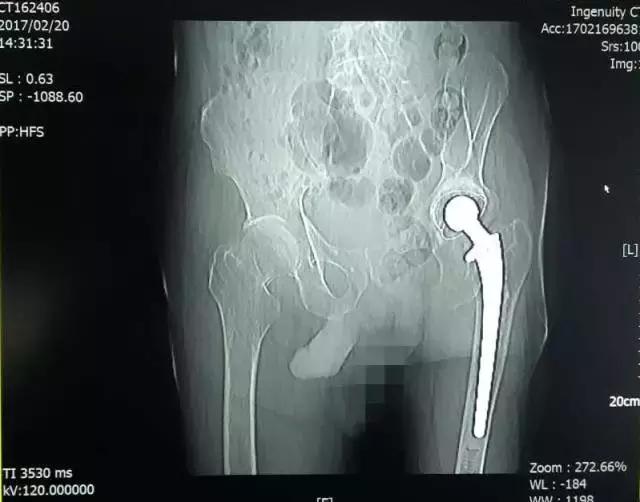

陶XX术前CT

患者陶XX,男,91岁,患者因跌倒致右髋部疼痛、功能障碍3小时就诊。

入院诊断:1.右股骨颈骨折(头下型); 2.骨质疏松症(重度);3.左侧人工全髋关节置换术后。

诊疗措施:患者因右侧股骨颈骨折行右侧人工股骨头置换术。科室专家根据患者情况,以右大粗隆顶点为中点,取右髋后外侧入路,放置合适人工股骨头复位,关节活动度及稳定性合适,术中无副损伤,术后右髋部疼痛明显减轻。

1个月后随访,患者功能改善,生活质量良好。